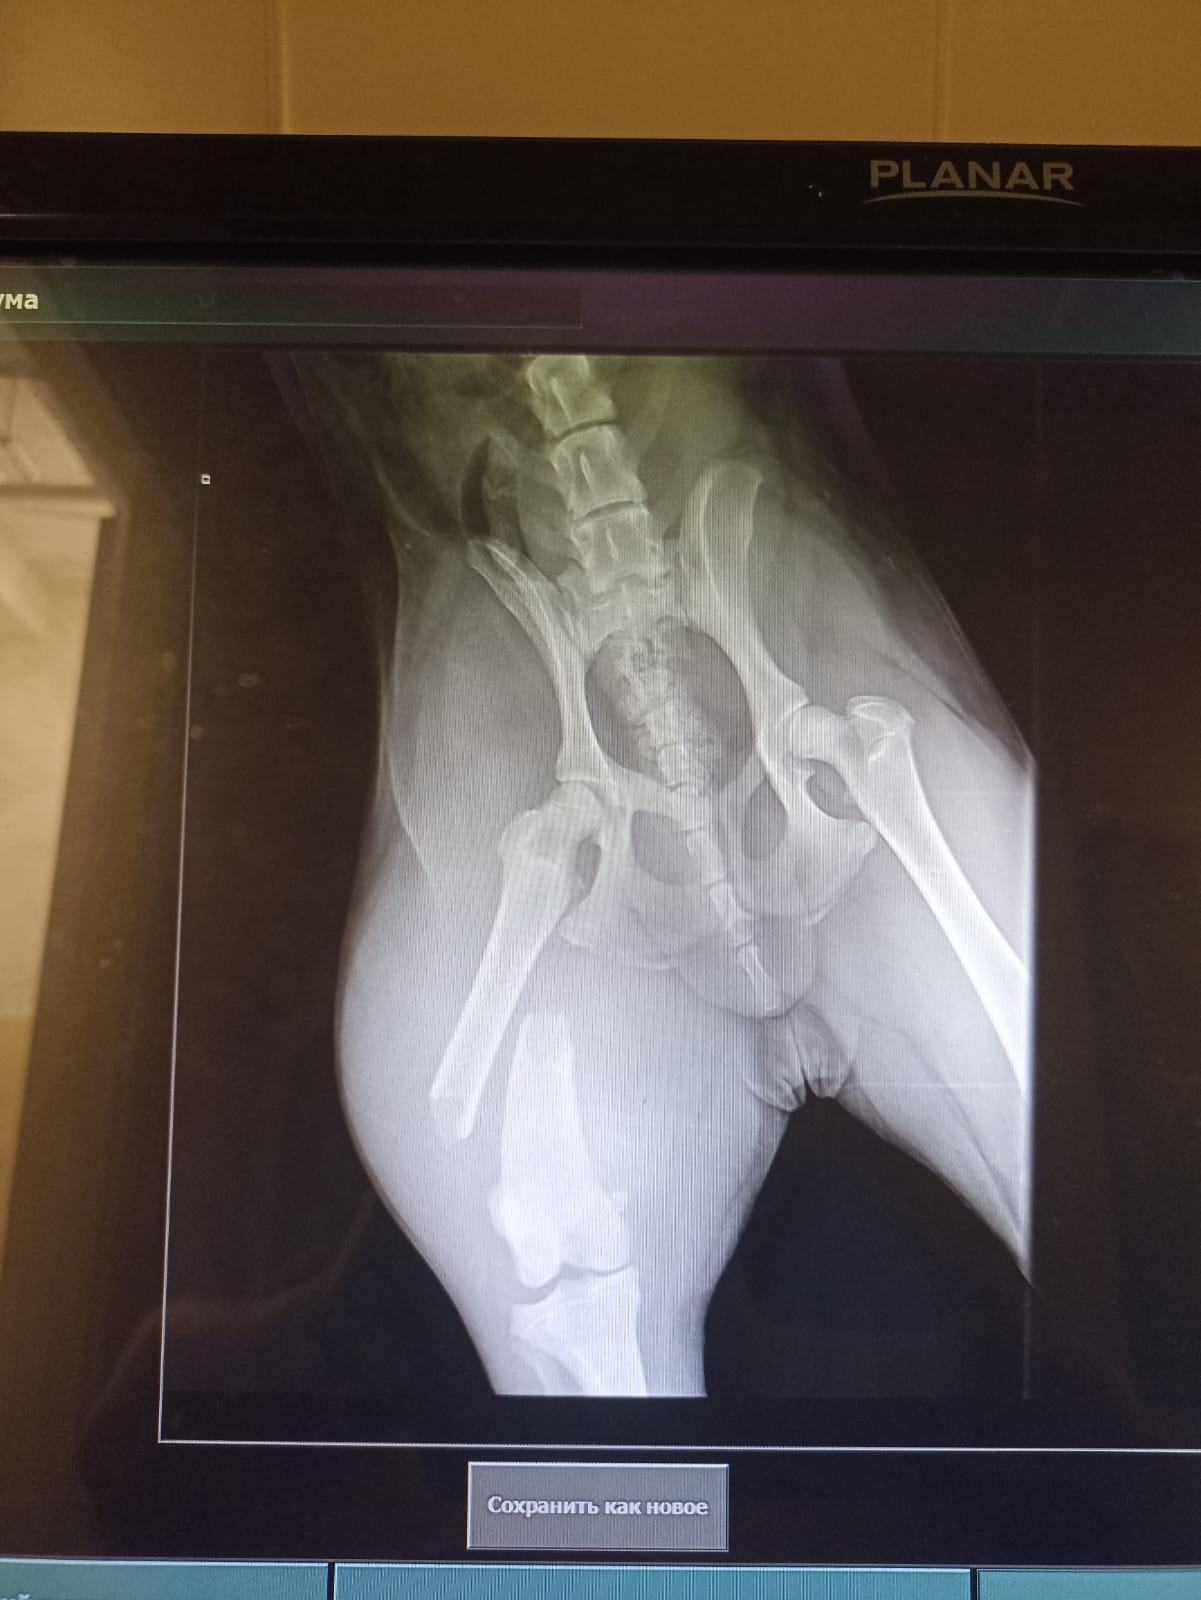

Через 2 недели контрольный рентген и снятие швов.

на 19-е записались на контрольный рентген и снятие швов.